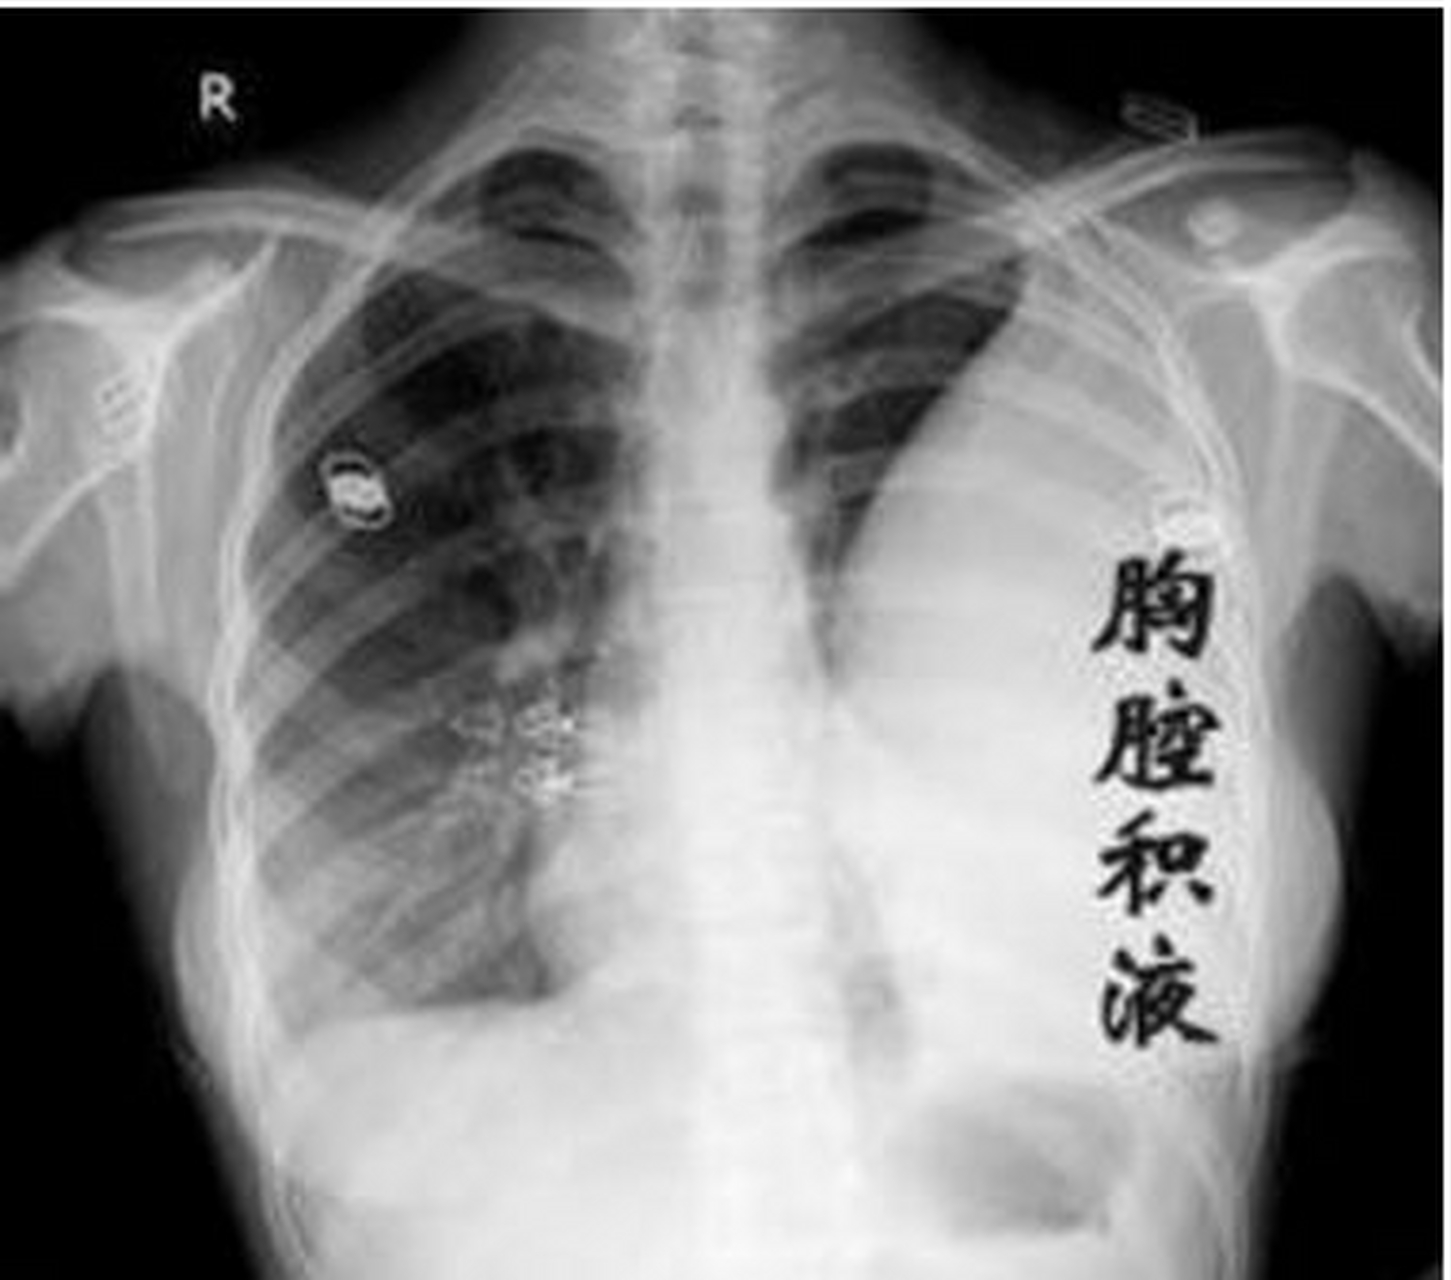

结核性胸膜炎二 #胸膜炎# 我是用的胸腔闭式引流 第一天胸水引流: 医